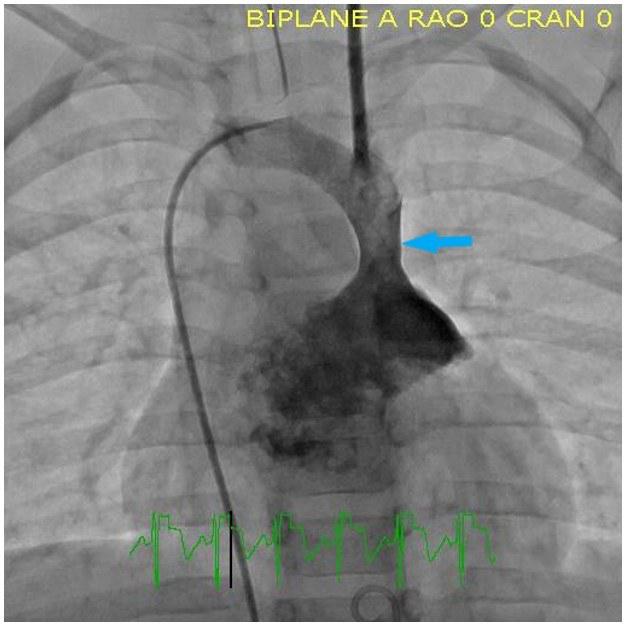

A 12-month-old boy presented for evaluation of recurrent bronchiolitis and hypoxemia. He was repeatedly admitted for acute respiratory failure at age 6, 9 and 11 months old. At 6 and 9 months of age he was positive for RSV but there was no clear infectious source in the third admission. He required oxygen support with all admissions. He had a normal echocardiogram at 2 and 11 months of age. At 13 months old he was seen by his pediatrician and noted to have an oxygen saturation of 88% on room air with no clear inciting illness which prompted another admission and pulmonary consultation. CT of the chest demonstrated the following:

What abnormality does the above chest CT reveal? What is the next best test to evaluate this abnormality?

B. Persistent left superior vena cava and cardiac catheterization